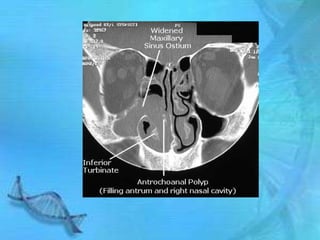

Classification of polyps according to site of

origion

•    1. Antrochoanal

– a. Single, Unilateral

– b. Can originate from maxillary

sinus near ostium

– It has 3 parts

Antral which is a thin stalk

Choanal which is round and globular

Nasal which is flat from side to side

2) CT Scan show soft tissues arising from left maxillary sinus involving nasal cavity and nasopharynx

Antrochoanal polp involvinf left maxillary sinus nasal cavity